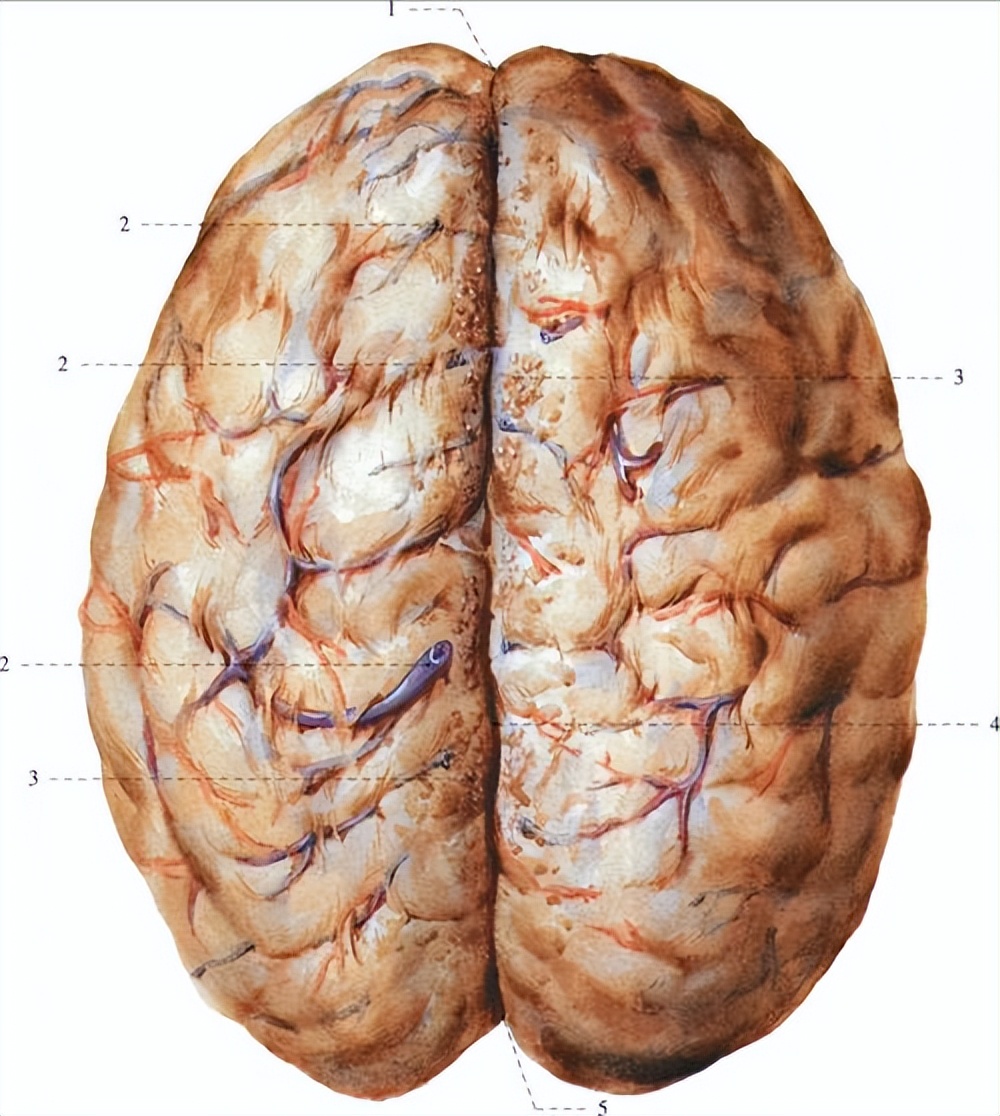

通常,动脉瘤破裂后,蛛网膜下腔内的积血激发一系列反应,其中自然包括对RBC的清除,血管内皮细胞表面快速表达特定的细胞黏附分子,以 使循环中的巨噬细胞和中性粒细胞进入蛛网膜下腔发挥吞噬作用 。

随后脑脊液中死亡的白细胞和被吞噬的红细胞体可释放大量有害物质包括内皮素、氧自由基、血红蛋白/亚铁血红素(及降解产物)等等, 这些物质的释放会促进炎症反应通路和内皮细胞介导的血栓形成 ,后者更是能够形成激活血小板、导致微血栓形成的正反馈通路。